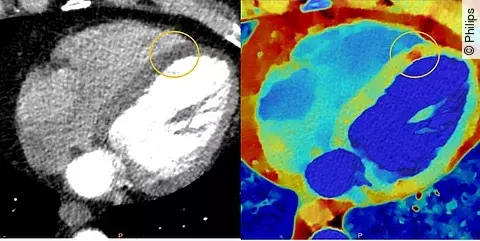

Bislang kam die detektorbasierte spektrale CT vor allem in der Onkologie zum Einsatz. Doch der potenzielle Nutzen ist auch für zahlreiche andere Fächer groß. Das neue Philips System erlaubt eine breitere Anwendung als die Vorgängergeneration, damit alle Patientengruppen einschließlich Kinder, Jugendliche und Menschen mit Adipositas von den Vorteilen profitieren können. Bei kardiologischen Fragestellungen liefert es selbst bei Patientinnen und Patienten mit hoher und unregelmäßiger Herzfrequenz eine qualitativ hochwertige Darstellung der Anatomie.